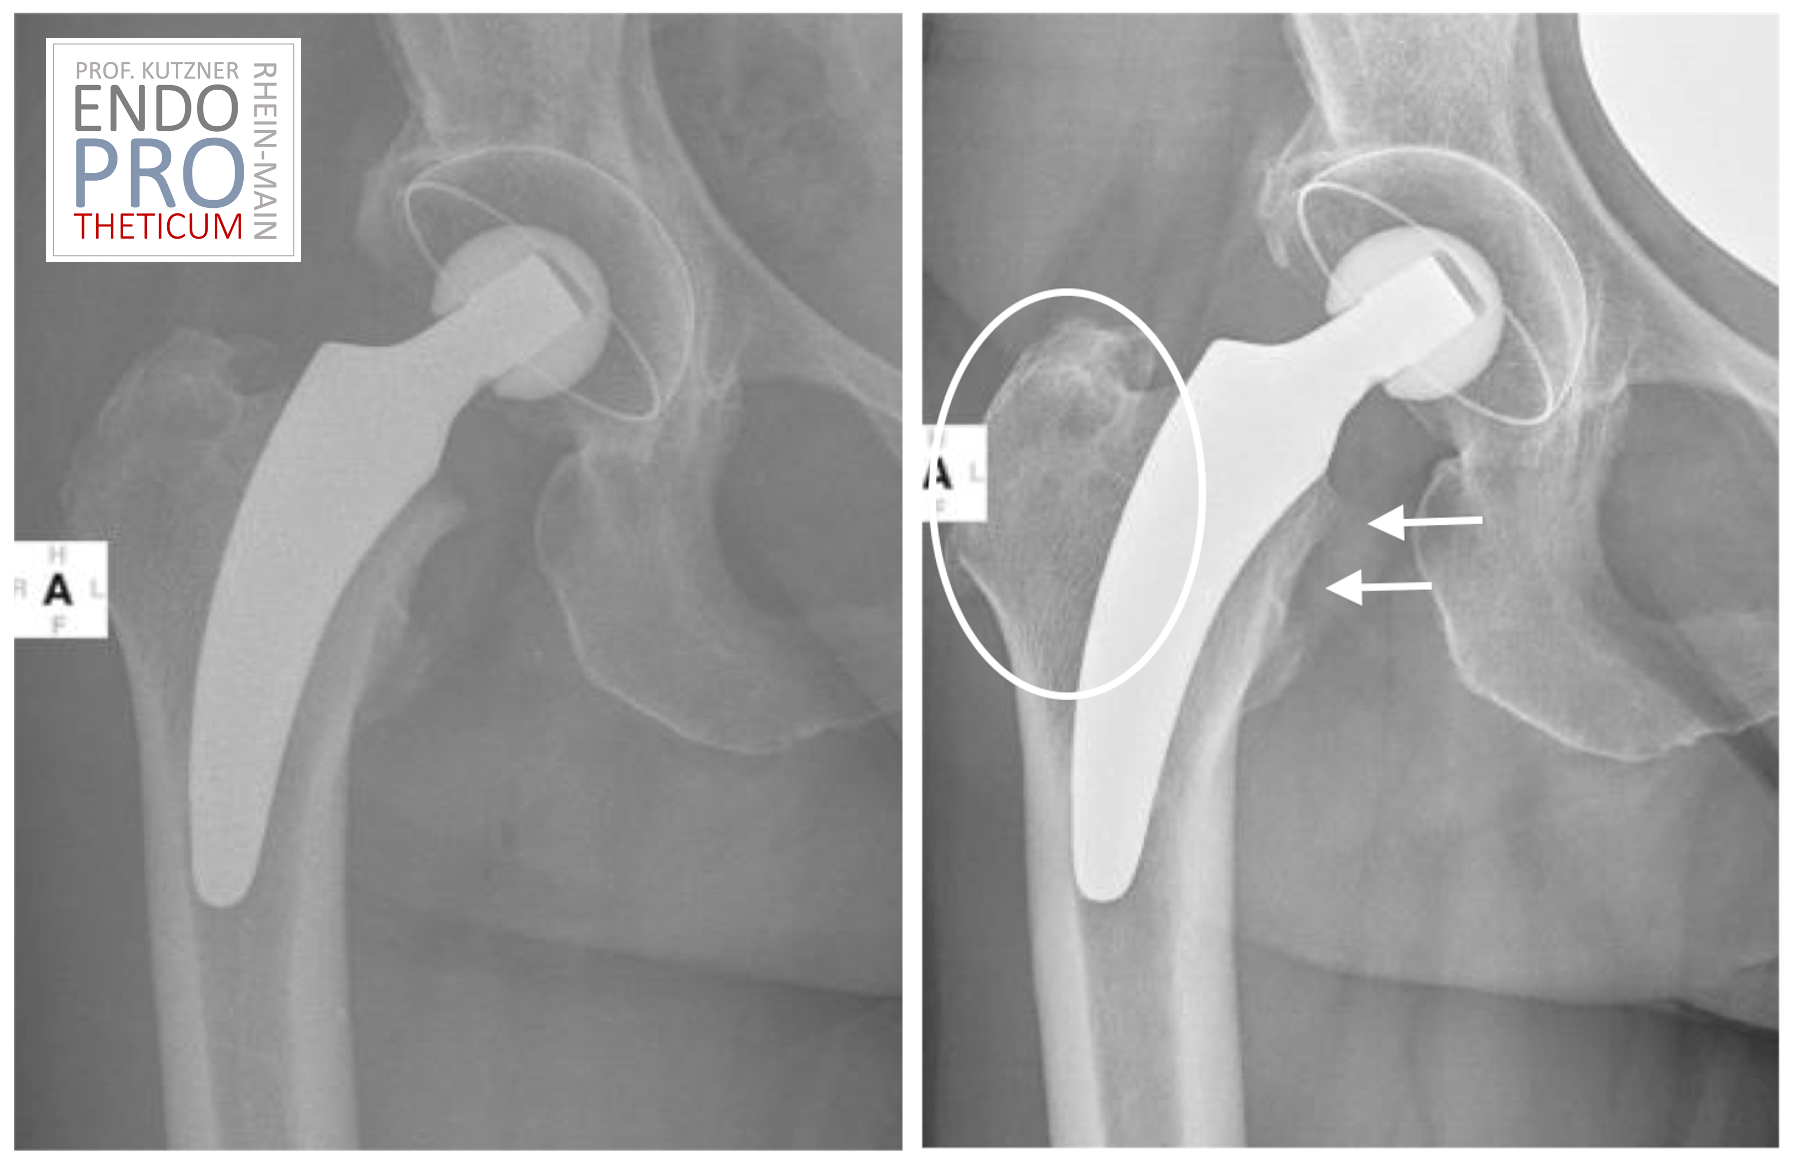

Kurzschaftprothesen sind Implantate, die speziell für die Hüftendoprothetik entwickelt wurden und eine verkürzte Schaftlänge im Vergleich zu herkömmlichen Implantaten aufweisen. Sie werden in den Oberschenkelknochen eingefügt, um beschädigtes oder erkranktes Gewebe zu ersetzen und die Funktion des Hüftgelenks wiederherzustellen. Kurzschaftprothesen bieten eine verbesserte Stabilität und Beweglichkeit des Hüftgelenks, was zu einer schnelleren Genesung und weniger postoperativen Beschwerden führen kann.

Kurzschaftprothesen bieten eine Reihe von potenziellen Vorteilen für Patienten. Dazu gehören eine schnellere Genesung aufgrund der minimalinvasiven Operationstechnik, eine verbesserte Stabilität des Hüftgelenks und eine geringere Wahrscheinlichkeit von Dislokationen oder Luxationen nach der Operation. Darüber hinaus erfordern sie oft weniger Knochenentfernung während der Operation, was die Integrität des Oberschenkelknochens erhalten kann.

Obwohl Kurzschaftprothesen viele potenzielle Vorteile bieten, sind sie nicht für jeden Patienten geeignet. Wie bei allen medizinischen Verfahren gibt es auch bei der Verwendung von Kurzschaftprothesen Risiken und Komplikationen, einschließlich Infektionen, Blutgerinnseln und Lockerung des Implantats. Es ist wichtig, diese Risiken mit Ihrem Arzt zu besprechen und eine gründliche Risiko-Nutzen-Analyse durchzuführen, um festzustellen, ob Kurzschaftprothesen die richtige Option für Sie sind.